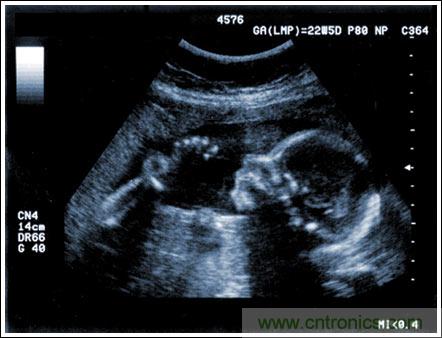

超聲成像系統(tǒng)及主要子功能電子元件的設(shè)計(jì)考慮

【導(dǎo)讀】該應(yīng)用筆記介紹了超聲成像系統(tǒng)的設(shè)計(jì)考慮,討論成像系統(tǒng)的小型化、低成本和便攜化的發(fā)展趨勢(shì),同時(shí)闡述了在小型系統(tǒng)中實(shí)現(xiàn)大型車載系統(tǒng)所具備的性能和診斷能力的重要條件。文章探討了超聲系統(tǒng)的子功能以及對(duì)電子元件的要求,重點(diǎn)討論了傳感器、高壓復(fù)用器、高壓發(fā)射機(jī)、成像通道接收機(jī)、數(shù)字波束成形、波束成形數(shù)字信號(hào)處理及顯示處理等。

通過(guò)發(fā)射超聲能量進(jìn)入人體,接收并處理返回的反射信號(hào),相控陣超聲系統(tǒng)可以生成體內(nèi)器官和結(jié)構(gòu)的圖像,映射血液流動(dòng)和組織運(yùn)動(dòng),同時(shí)提供高準(zhǔn)確度的血流速度信息。傳統(tǒng)設(shè)計(jì)中,構(gòu)建這樣的成像系統(tǒng)需要大量的高性能相控陣發(fā)射器和接收器,使得車載設(shè)備體積龐大且價(jià)格昂貴。近年來(lái),隨著集成工藝的進(jìn)步,設(shè)計(jì)人員能夠獲得小尺寸、低成本而且高度便攜的成像系統(tǒng)方案,并可達(dá)到接近大型成像設(shè)備的性能指標(biāo)。而新的設(shè)計(jì)挑戰(zhàn)依然存在,即在進(jìn)一步提高方案集成度的同時(shí)提高系統(tǒng)性能和診斷能力。